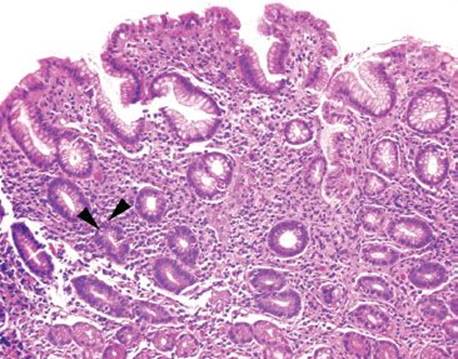

Figure 2.33 Acute gastritis example. An acute gastritis pattern refers to neutrophils in the gastric epithelium of the stomach (arrows). Acute gastritis pattern is an etiologically nonspecific pattern. This case features a single epithelial cell with nuclear and cytomegaly and smudged chromatin (arrowhead). A confirmatory CMV immunostain was reactive (not shown).

An acute gastritis pattern refers to neutrophils in the epithelium of the stomach (Fig. 2.33). This pattern can be accompanied by erosions, ulcerations, and marked reactive epithelial change. Although this injury pattern is etiologically nonspecific, it is most commonly seen in the setting of medication injury, infections (Helicobacter and CMV), and inflammatory bowel disease. This injury pattern can also be seen with iatrogenic injury (gastrotomy tube, postsurgical setting, chemoradiation), alcohol, and in association with polyps and infiltrating processes such as amyloidosis and neoplasms. This section will discuss the most common etiologies of the acute gastritis pattern and will present practical tips to sort out the individual etiologies.